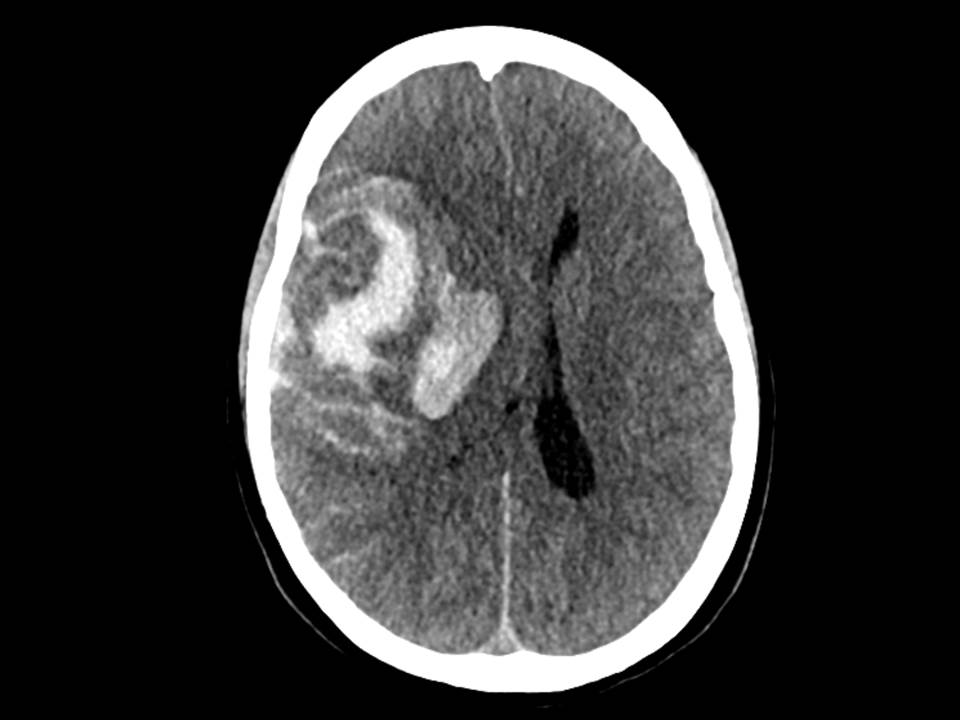

Pasienten ankom universitetssykehuset tre timer etter varsling fra lokalsykehuset. Ved mottak hadde pasienten bilateral mydriasis uten lysreaksjon. Behandling med mannitol ble igangsatt, og CT caput tatt umiddelbart etter ankomst viste progrediering av en stor intrakranial blødning med startende herniering (figur 2). Cerebral angiografi (TCD) var forenlig med opphørt blodsirkulasjon i hjernen, og videre tiltak ble vurdert som uhensiktsmessige.

Få dager etter denne hendelsen ble det meldt fra Rikshospitalet om flere tilfeller av alvorlige blodpropper og blødninger hos pasienter som hadde fått identisk vaksine. Også disse pasientene hadde lave trombocyttall, og i disse tilfellene klarte man å finne en sammenheng mellom hendelsene og vaksinen (1). Tilstanden er etter dette omtalt som vaksineindusert trombotisk trombocytopeni (VITT), som kjennetegnes av lave trombocyttall, trombedannelser og antistoff mot platefaktor 4 (1, 5). I lys av denne kunnskapen ble det gjort nye undersøkelser, og man fant også hos vår pasient tendens til trombedannelse med små tromber i sinus transversus, pannelapper og a. pulmonalis. Det ble også påvist antistoff mot platefaktor 4. Samlet sett er det derfor mye som taler for at dette var et tilfelle av vaksineindusert trombotisk trombocytopeni. Retrospektivt må man spørre seg om blødningen sett på CT representerte et venøst hemoragisk infarkt tilsvarende det som ble sett hos flere pasienter på Rikshospitalet (1), og om blødningskomponenten kan ha vært dominerende som følge av vaksineindusert trombotisk trombocytopeni. Et venøst infarkt kunne kanskje forklare pasientens hodepine.